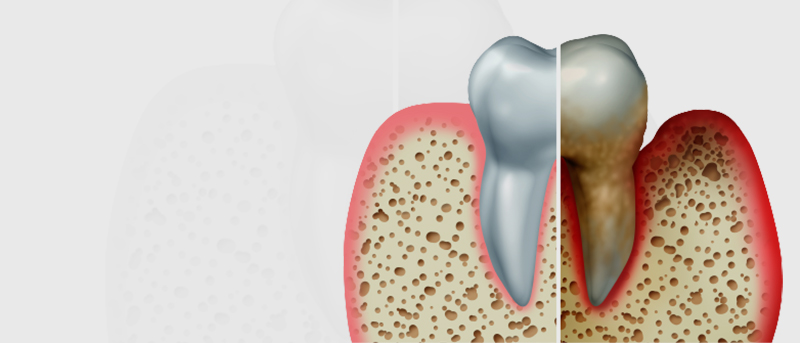

잇몸 전체가 무너져 동시다발적으로 죽어가던 치아들을 한꺼번에 살려 냅니다.